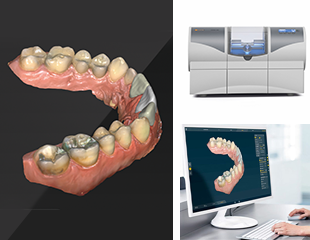

治療に必要な三種の神器

マイクロスコープ・CT・CAD-CAMシステム

CAD-CAMシステム

スピーディー!高耐久!

自然な美しい歯を実現しませんか。